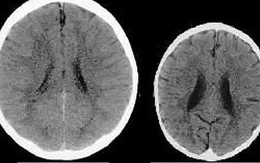

Bức ảnh não bộ của 2 em bé tiết lộ bí mật gây sốc về tình yêu thương của cha mẹ

Bức ảnh não bộ này hé lộ tầm quan trọng của việc một đứa trẻ được yêu thương ngay từ nhỏ.